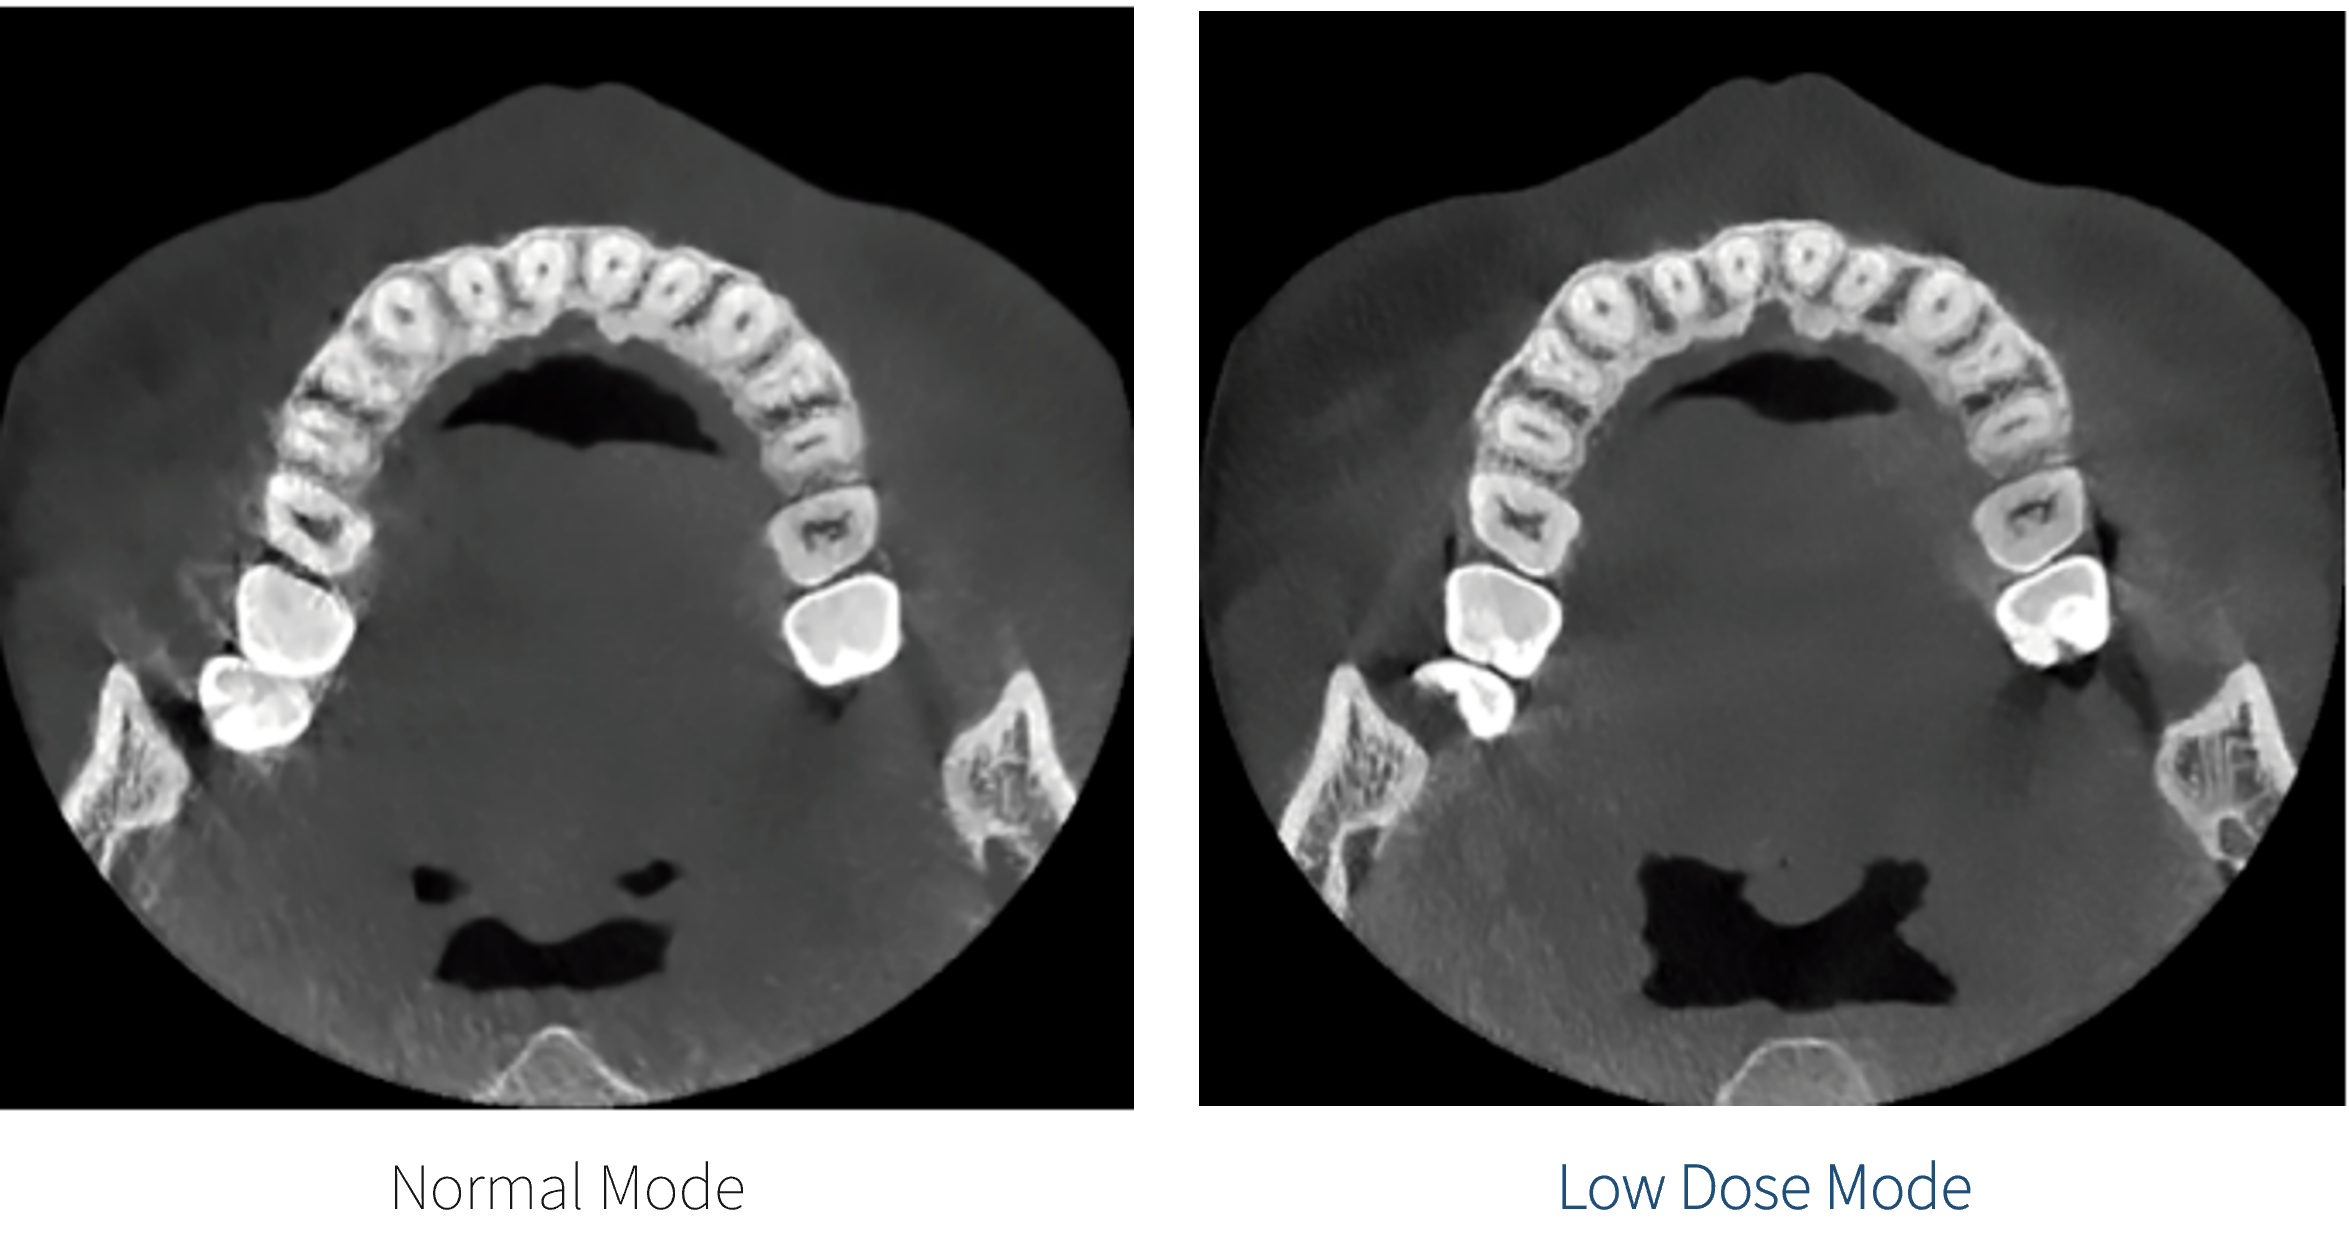

Ultra-Low Radiation Dose

Low dose mode captures diagnostic quality CBCT images while reducing patient radiation exposure.

* 4T Model Only